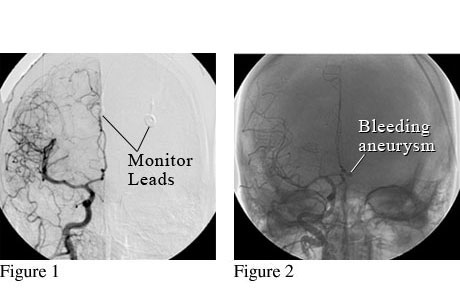

Figure 1 shows normal blood flow in the arteries on one side of the brain. Figure 2 shows a weak spot in a blood vessel (aneurysm) that is bleeding.